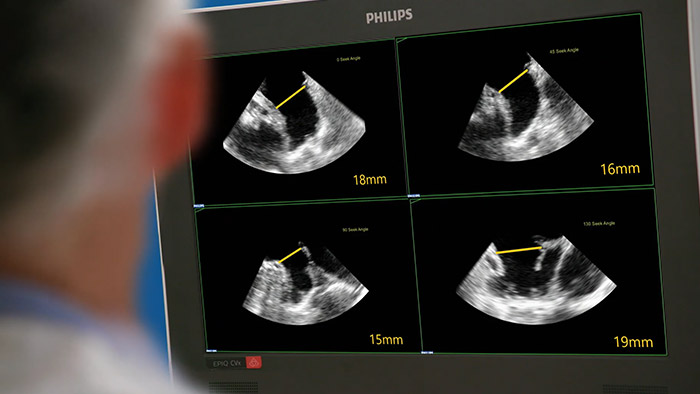

Assessing the left atrial appendage quickly, easily, intuitively. The Philips LAA solution on EPIQ CVxi.

EchoNavigator reorients and combines ultrasound and X-ray information into a single augmented visualization for guidance and device-tissue relationship assessment. In LAA occlusion EchoNavigator enables the following to elevate confidence and boost efficiency: